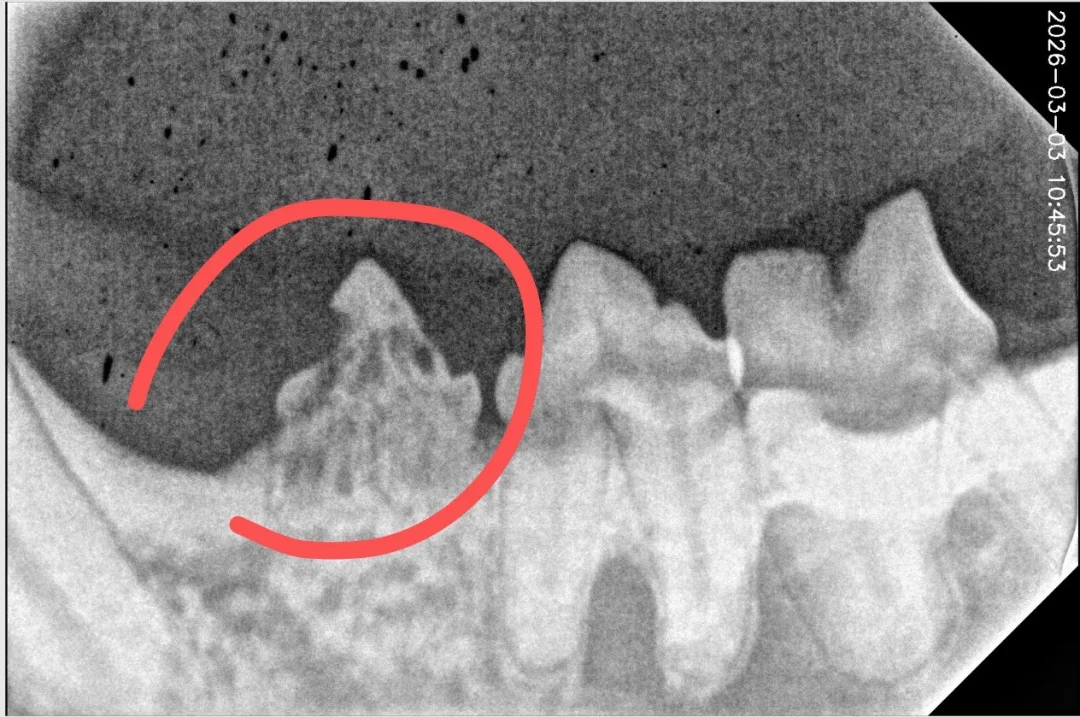

猫的牙吸收,拍片才知道猫的痛

转网友分享,猫拍的牙片,牙吸收,引发牙龈发炎了,这种情况吃药没用,拔牙才行。大家留意自己的猫,多检查猫口腔